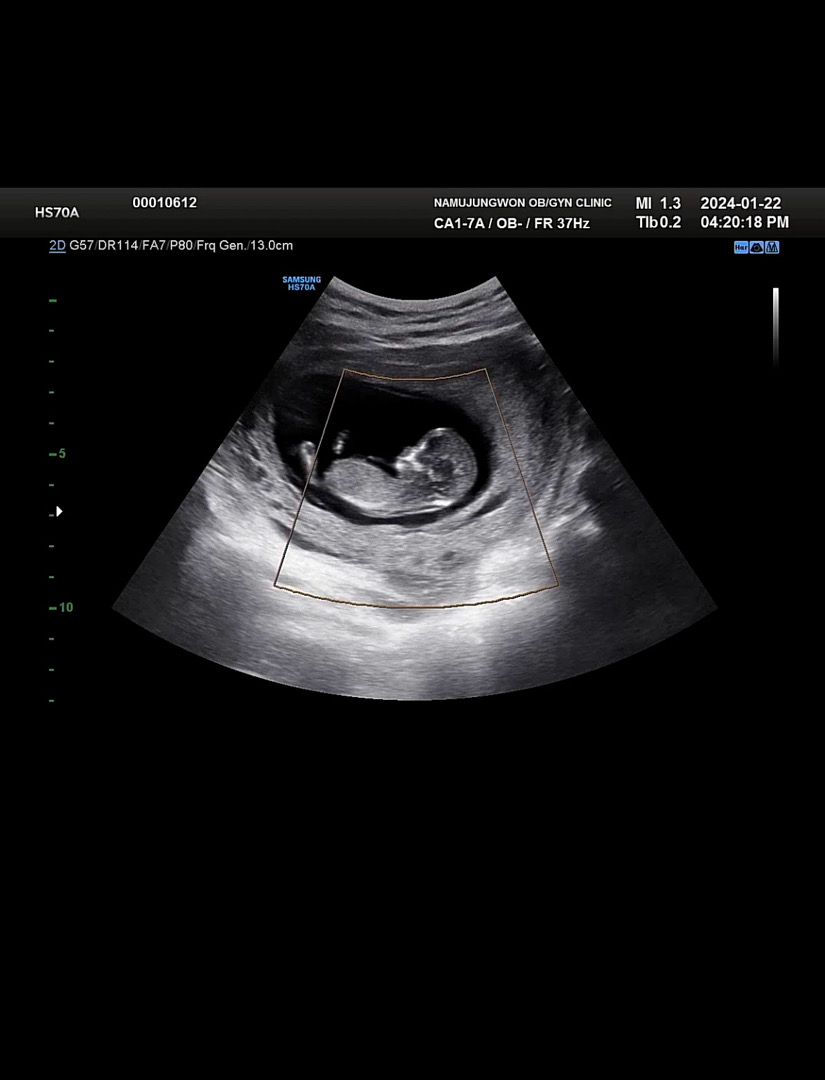

11주6일각도법 한번만 봐주세요

이걸로 봐서 아들인지 딸인지 알수있을까요